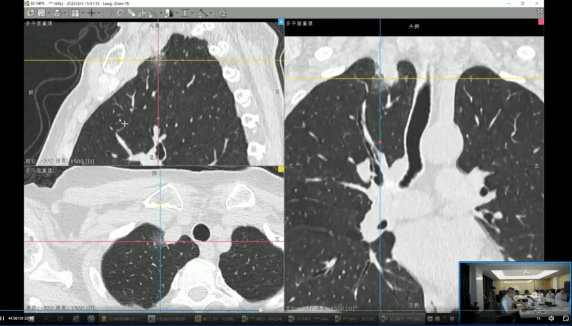

AI与影像技术创新:集团积极布局人工智能与前沿影像技术,以智能化、精准化驱动诊断产品升级。在AI智能诊断领域,陆续推出CT骨密度智能分析、CT冠脉钙化积分评估、CT-FFR(无创血流储备分数)分析等多款AI辅助诊断产品,提升诊断效率与一致性。在影像检查技术方面,成功推出并应用了磁共振全身成像(MMR)、普美显动态增强磁共振(DCE-MRI)肝癌早筛、脑认知功能AI辅助解读、心脏全面磁共振检查(CMR)以及儿童生长发育综合评估等一系列前沿检查与评估方案,显著拓展了疾病的早期发现与精准评估能力。

12月,高尚健康集团上海中心与上海长征医院携手,以“基于PET/MR一体化影像数据及AI后处理的盆腔解剖学三维重建手术规划的临床实践与应用”为研究方向,通过对上百例患者开展结直肠专项筛查,完成了相应的科研论证工作。